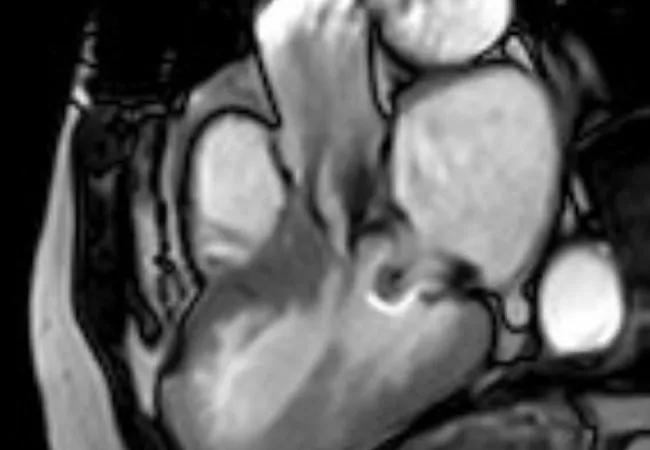

An echocardiogram performed at Cleveland Clinic showed a fixed, elevated gradient across her LVOT secondary to retained anterior mitral leaflet. Her resting LVOT gradient was 52 mm Hg. The gradient increased to 56 mm Hg with Valsalva maneuver and 70 mm Hg with stress. The interventricular septum was noted to be 1.5 cm. There was no paravalvular leak or mitral regurgitation. Cardiac MRI confirmed the outflow obstruction secondary to a completely retained leaflet and subvalvular apparatus (Figure 1).

Figure 1

Figure 1. Cardiac MRIs from the first patient. Top image demonstrates a narrow left ventricular outflow tract (LVOT) (blue line) in diastole. Its diameter is 9 mm at the narrowest point, in contrast to 24 mm at the level of the aortic valve. Red arrow indicates the prosthetic mitral valve strut; yellow arrow indicates chordae to the retained anterior mitral leaflet. Bottom image demonstrates turbulent flow through the LVOT in systole.